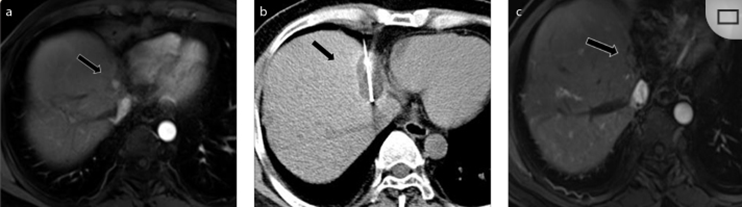

冷冻消融胆囊附近肿瘤病灶

(A)动脉期 MRI 显示胆囊附近有外周增强病变(箭头)。

(B)手术过程中 CT 显示冷冻探针位于病灶内。

(C)消融后,术后 1 个月CT 显示完全消融(箭头)。